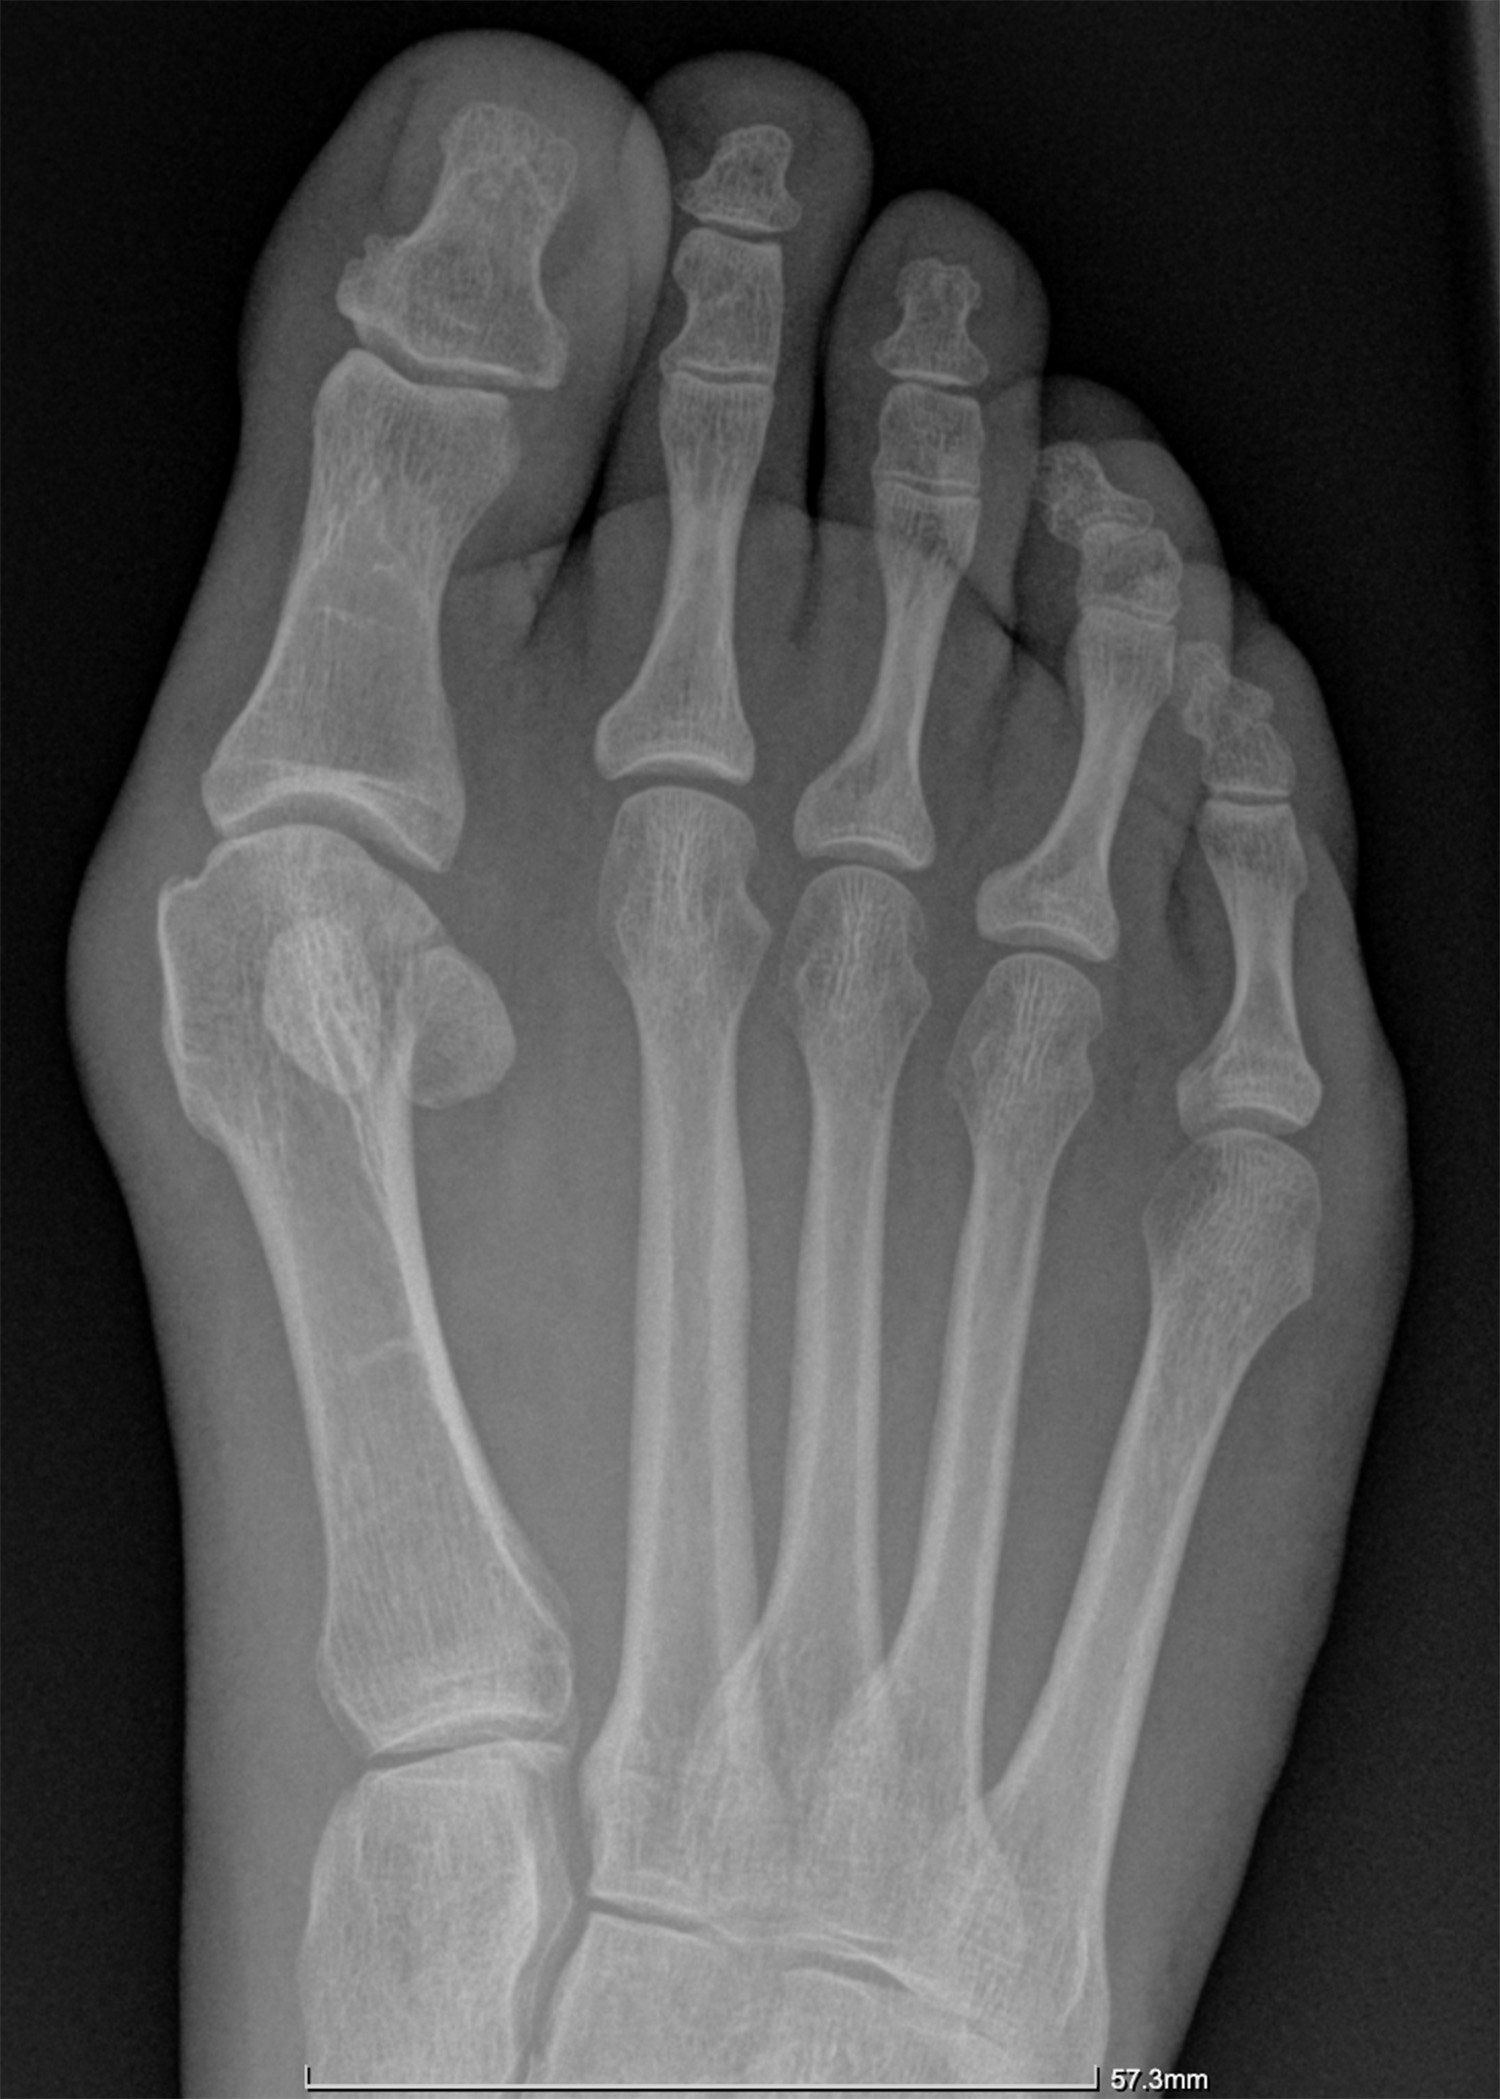

Hallux Valgus (Bunion)

To reduce pain and deformity in bunions.

To straighten the big toe.

Indications for the procedure

Painful bunions, unable to t into shoes, blisters, risk of ulceration.